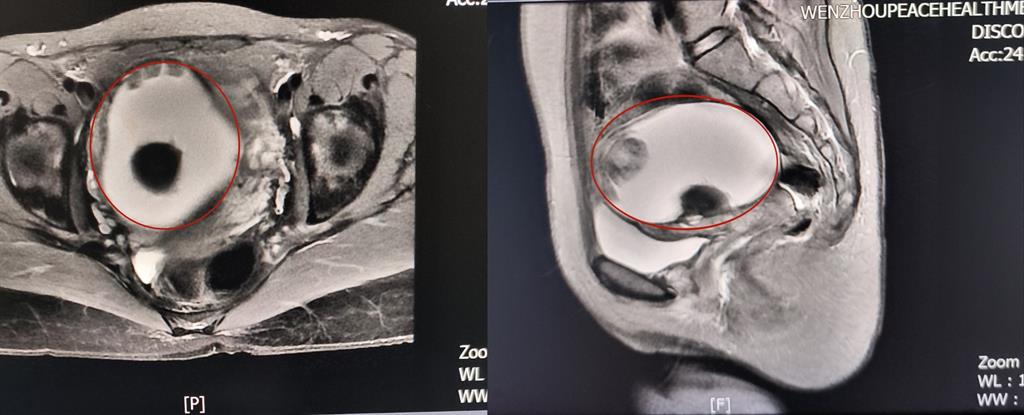

前不久,溫州某高校外籍教師A女士來(lái)到和平國(guó)際醫(yī)院體檢與健康管理中心進(jìn)行深度體檢。B超提示“子宮右側(cè)附件區(qū)囊性塊,大小約82*79*88mm”和平國(guó)際醫(yī)院婦科主任醫(yī)師方軼萍發(fā)現(xiàn),A女士還有三項(xiàng)腫瘤標(biāo)志物數(shù)據(jù)超標(biāo)(甚至高出正常值兩倍)。

卵巢腫瘤?為進(jìn)一步明確診斷,A女士在方主任建議下做了增強(qiáng)磁共振,影像結(jié)果提示:盆腔右側(cè)團(tuán)塊狀占位伴多發(fā)成熟脂肪成分大小約89*100*71mm,考慮畸胎瘤可能性大。謎團(tuán)逐漸解開(kāi),原來(lái)那個(gè)“怪胎”可能是畸胎瘤在作祟。

回家考慮后,A女士決定來(lái)和平國(guó)際醫(yī)院手術(shù)治療。“畸胎瘤大部分是良性,而且患者未婚未育,評(píng)估后我們決定采用微創(chuàng)的治療方案——腹腔鏡下畸胎瘤剝除術(shù)。”方主任講到,這樣不僅創(chuàng)傷小,還能保護(hù)患者的生育能力。

因腫物與周圍組織粘連致密暴露困難,這極考驗(yàn)主刀醫(yī)生的經(jīng)驗(yàn)和專業(yè)技術(shù)。為避免腫瘤破裂及血管損傷,和平國(guó)際醫(yī)院婦科團(tuán)隊(duì)主任醫(yī)師方軼萍、副主任醫(yī)師周婷在腹腔鏡下精細(xì)操作,完整切除囊腫,術(shù)中快速冰凍病理檢查結(jié)果證實(shí):成熟型囊性畸胎瘤(良性)。